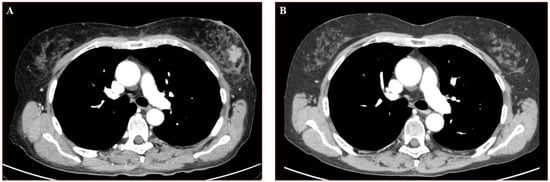

1. Case Presentation